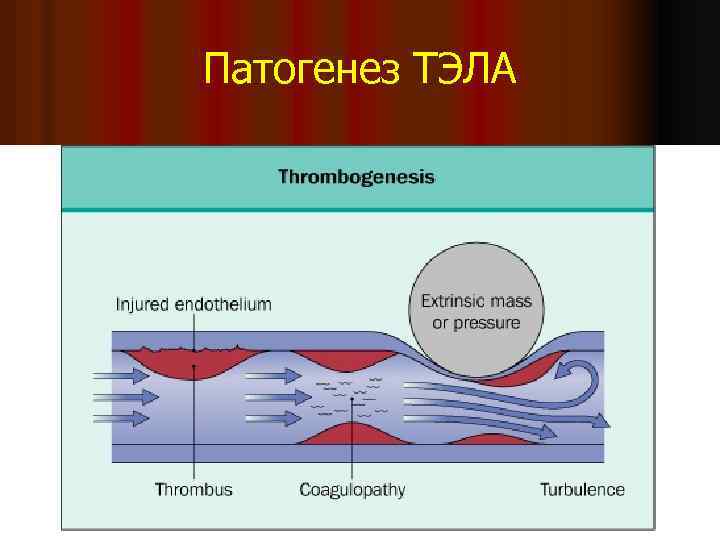

Патогенез ТЭЛА

Патогенез ТЭЛА